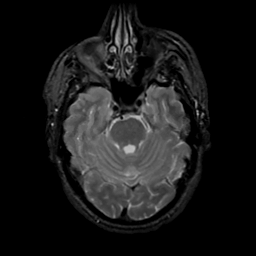

MR Study #13, May 19, 1991 -- Slice #15